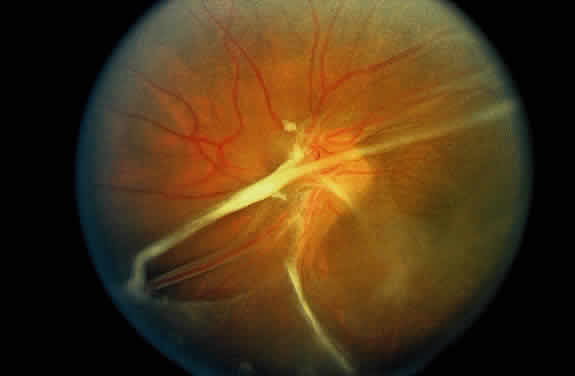

A varying degree of peripheral retinal nonperfusion is present in all patients with this disease. The nonperfusion generally is confluent and sharply demarcated from the posterior perfused retina (Fig. 3). Fine white lines representing the remains of obliterated large vessels (ghost vessels) often are seen in the area of nonperfusion. The temporal retina is most commonly affected.

Fig. 3. Fluorescein angiogram of the peripheral retina demonstrates the junction of normally perfused retinal vessels adjacent to an area of nonperfused retina. Notice the vascular abnormalities at the junction.

Elliot and Spitnas and colleagues have documented the abnormalities at the junction between the anteroperipheral nonperfused and the posterior perfused retina.9,10 Intraretinal hemorrhages often first appear in the affected area, followed by an increase in vascular tortuosity with frequent collateral formation around occluded vessels (see Fig. 3). Microaneurysms, arteriovenous shunts, and venous beading are commonly seen at the junction (Fig. 4). Fluorescein angiography enhances these abnormalities and often demonstrates staining at the stumps of obliterated vessels.

Fig. 4. Fluorescein angiogram demonstrating severe nonperfusion involving the macula. In this case, the macular nonperfusion was responsible for loss of central vision.